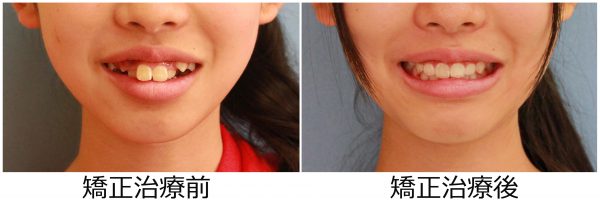

13歳 女性 「 八重歯 出っ歯を 治したい」 ( 上下顎叢生)

矯正治療のために 上下左右の 抜歯を行い

段差を解消し、前歯を後方に移動させました。

2018年の7月7日にスタートして 2019年の11月2日に 終 了しました。

治療期間は 16か月でした。

歯ならびは綺麗に整い ”八重歯” と ”出っ歯” 感は解消されました。

口元がスッキリ しました。

口もとの 印象が 大きく変わり お母さんが一番喜ばれていました。

素敵な笑顔になりました! (#^.^#)

まだ 15歳 (^◇^)! この笑顔で

13歳 女性 叢生を伴う 上顎前突症 治療期間16か月 唇側矯正装置(ホワイトワイヤー)を使用した上下顎第一小臼歯抜歯治療 参考治療費 約65万円 (精密検査から終了まで) 矯正治療に伴う副作用の歯肉退縮、知覚過敏、失活、歯根吸収などは認められませんでした。